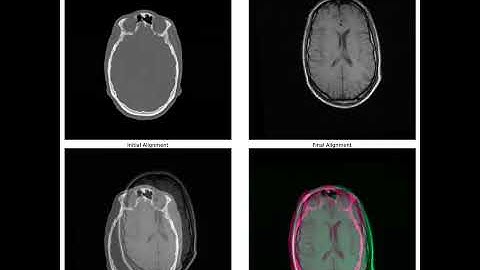

A tutorial on image registration in Python